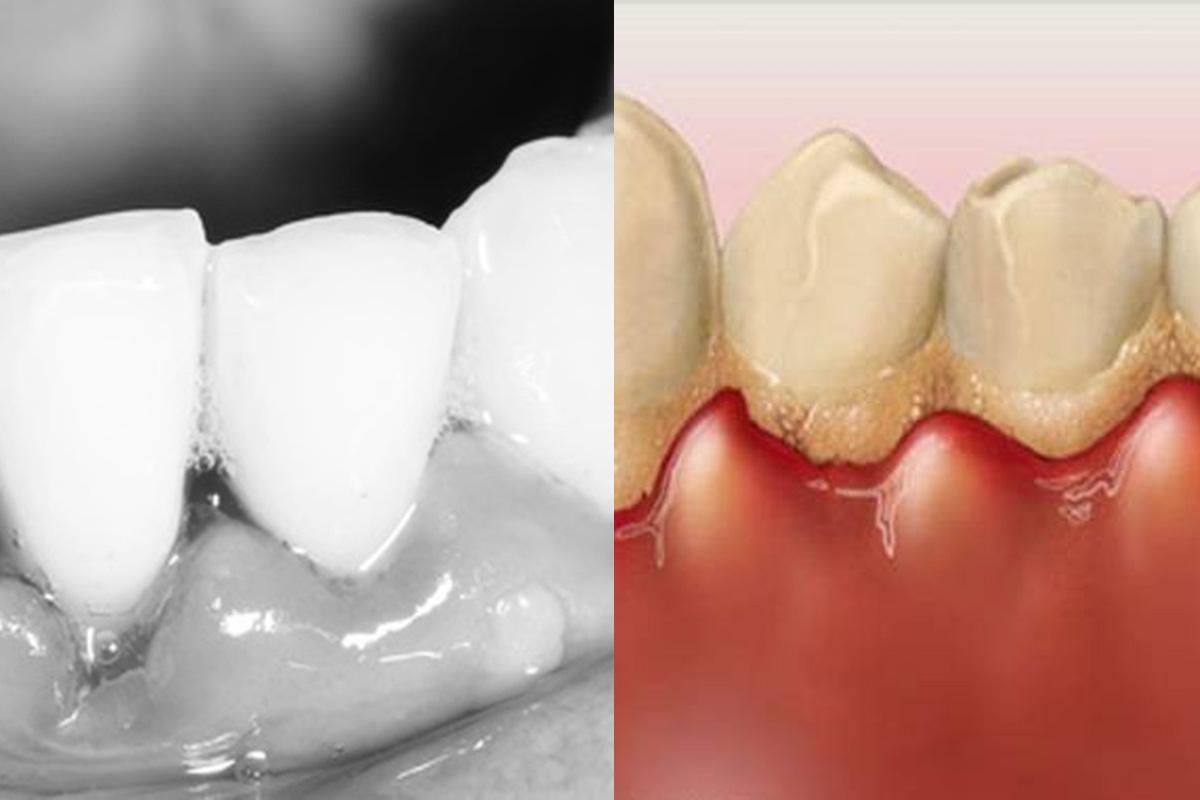

Dantenų uždegimas vystosi labai lėtai, todėl iš pradžių, pacientas gali net neįtarti, jog jį užklupo ši problema. Vienas akivaizdžiausių požymių, bylojančių apie dantenų uždegimą, yra jų spalva. Pirmiausia pastebimas lengvas paraudimas, vėliau spalva intensyvėja, kol pasiekia melsvai raudoną arba mėlyną spalvą. Nelieka sveikam dantenų paviršiui būdingo vaizdo. Dantenos iš pradžių būna minkštos, vėliau lengvai patinsta, o ligai progresuojant – sukietėja. Sutrinka kraujotaka, dantenų audinys keičia kontūrą, padidėja, todėl pagilėja kišenės. Net po lengvo prisilietimo šepetėliu, prasideda kraujavimas,kai kuriais atvejais jaučiamas skausmas.

Kokios yra sveikos, dantenų uždegimo nepaliestos dantenos?

• jų struktūra primena apelsino žievelę;

• nekraujuoja, nėra jautrios;

• tvirtos;

• rausvos arba balkšvos spalvos.